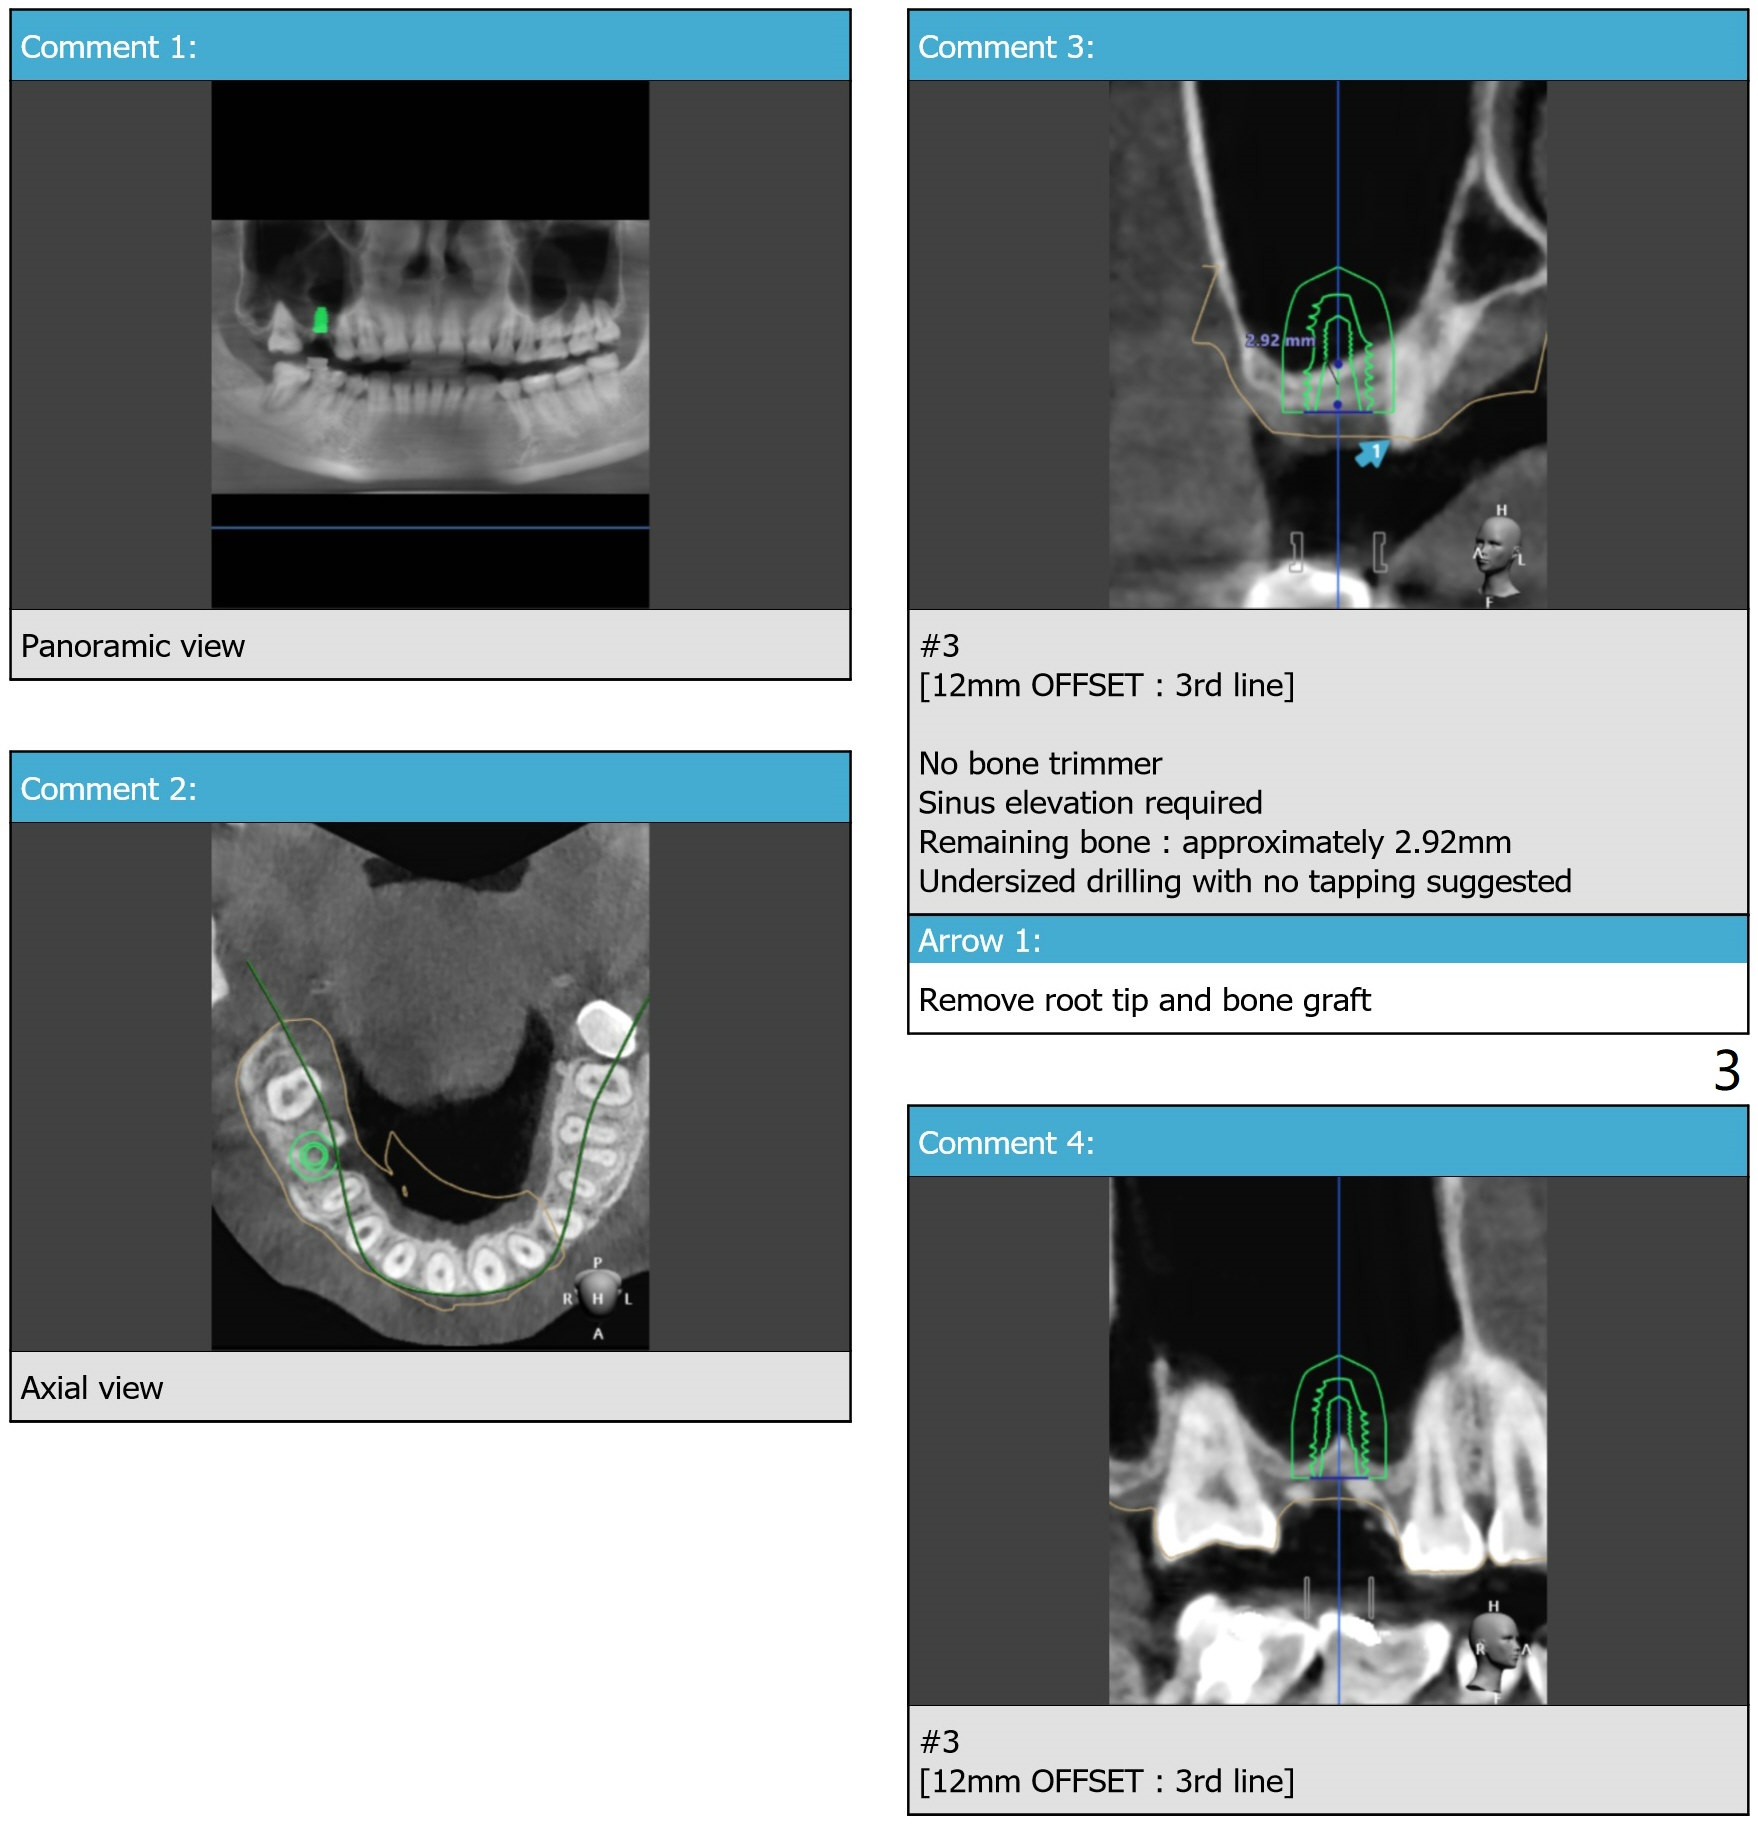

Internal Sinus Lift   M

Return to Upper Molar Immediate Implant, Prevent Molar Periimplantitis (Protocols, Table), Trajectory II, No Antibiotic